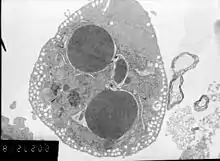

Methods for distinguishing apoptotic from necrotic (necroptotic) cells

In order to perform analysis of apoptotic versus necrotic (necroptotic) cells, one can do analysis of morphology by label-free live cell imaging, time-lapse microscopy, flow fluorocytometry, and transmission electron microscopy. There are also various biochemical techniques for analysis of cell surface markers (phosphatidylserine exposure versus cell permeability by flow cytometry), cellular markers such as DNA fragmentation[70] (flow cytometry),[71] caspase activation, Bid cleavage, and cytochrome c release (Western blotting). It is important to know how primary and secondary necrotic cells can be distinguished by analysis of supernatant for caspases, HMGB1, and release of cytokeratin 18. However, no distinct surface or biochemical markers of necrotic cell death have been identified yet, and only negative markers are available. These include absence of apoptotic markers (caspase activation, cytochrome c release, and oligonucleosomal DNA fragmentation) and differential kinetics of cell death markers (phosphatidylserine exposure and cell membrane permeabilization). A selection of techniques that can be used to distinguish apoptosis from necroptotic cells could be found in these references.[72][73][74][75]